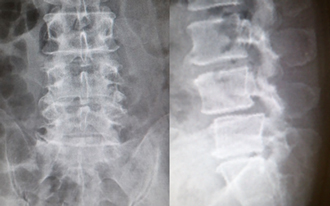

第4腰椎に前屈時に増強するすべりを認め不安定性を示しています。

MIS-TLIF(低侵襲腰椎後方椎体間固定術) 椎間板にケージと言われるスペーサーが挿入され、また経皮的に椎弓根スクリューの挿入とロッドの連結がなされ、第4腰椎のすべりが矯正され固定されています。